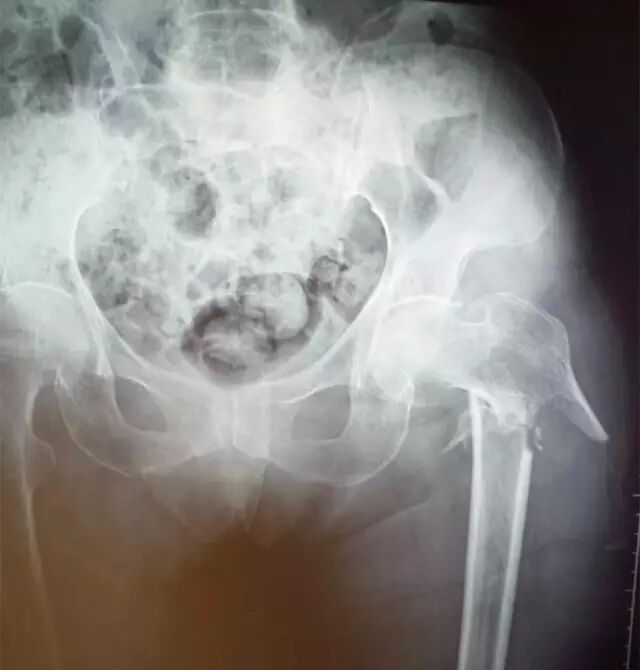

↑图:患者术前拍片情况